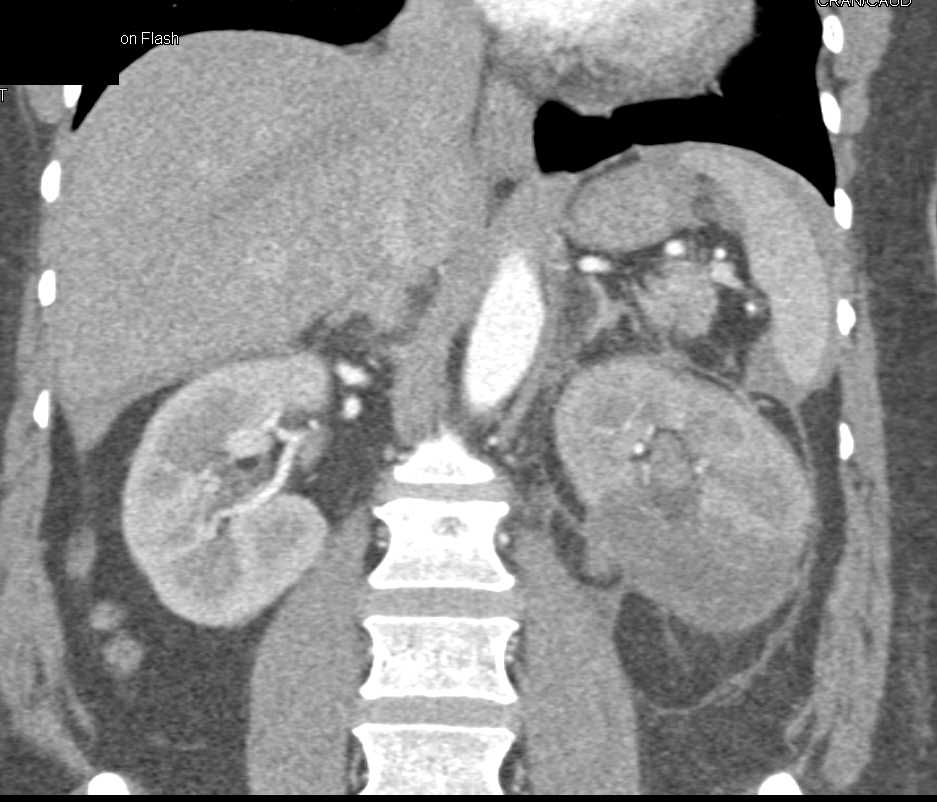

Acute Pyelonephritis Right Kidney